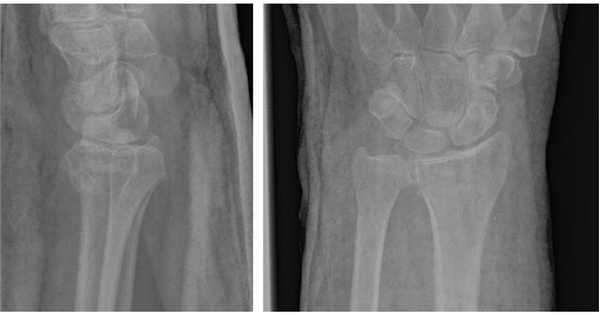

На представленной рентгенограмме не тренированный глаз может вообще не увидеть перелома, хотя врач травматолог и квалифицированный рентгенолог заметят насколько «просела» суставная поверхность лучевой кости, и отметят, что она развёрнута в тыльную сторону на 10 градусов (в норме она должна смотреть в ладонную сторону). Если присмотреться повнимательнее становятся видны линии перелома.

Намного более отчётливо степень нестабильности этих костных фрагментов видна под ЭОП-ом при выполнении функциональных проб. При тыльном сгибании определяется значительное количество мелких фрагментов тыльной кортикальной пластинки и внутрисуставной, оскольчатый характер перелома.

Рентгенография лучезапястного сустава. Перелом дистального метаэпифиза лучевой кости со смещением отломков.